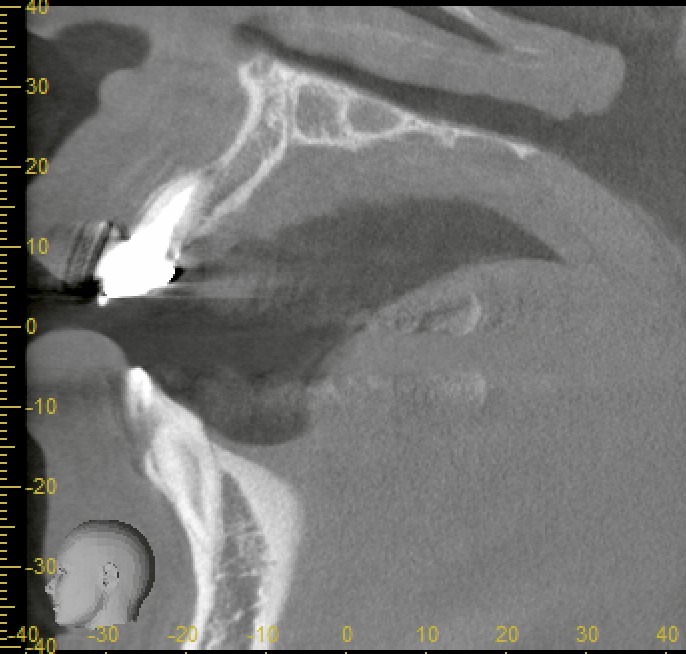

CT撮影により精査したところ、唇側の骨(前側の骨)が大きく欠損していることが確認されました。前歯は見た目にも大きく影響するため、できるだけ早く、そして審美性を保ちながら治療を進める必要があります。

CT所見の通り、唇側の骨が欠損していたため、インプラント埋入後にその部位に骨補填材を用いた骨造成を行いました。